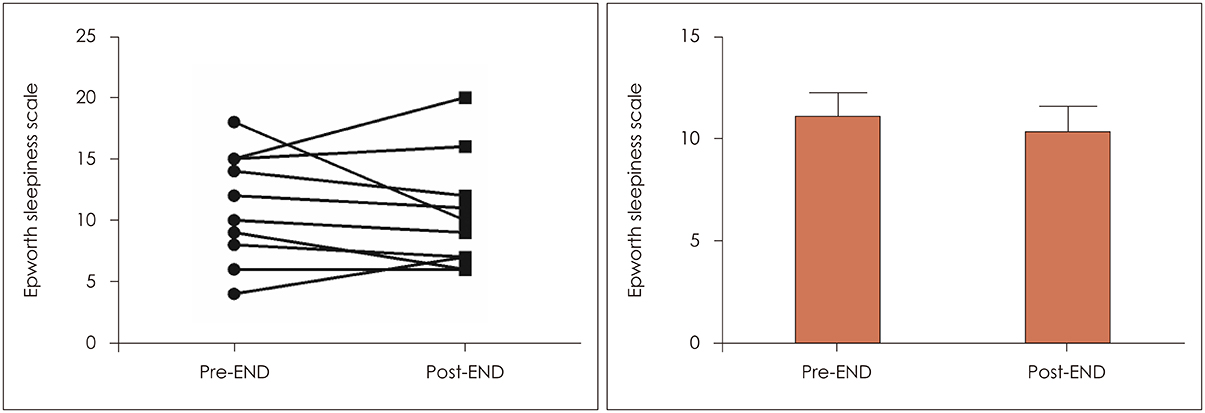

In 13 patients with OSA, changes of total nasal volume (TNV) and minimal cross-sectional area (MCA) before and after END use were evaluated. The change in peak nasal inspiratory flow (PNIF) was also measured. Subjects completed Epworth Sleepiness Scale questionnaire before and 2 weeks after END use. Finally, changes in apnea-hypopnea index (AHI), respiratory distress index (RDI), oxygen desaturation index (ODI), sleep time, sleep position and loudness of snoring (in decibels) were obtained by repetitive portable polysomnography.

RESULTS

After END use, TNV (11.4±3.1 cm3 to 19.4±5.7 cm3) and MCA (0.7±0.2 cm2 to 0.9±0.1 cm2) increased significantly (p=0.001). PNIF also increased significantly after END (147.3±39.5 to 194.6±57.6 liter/min, p=0.001). Among 11 patients undergoing 2-week follow-up, 7 reported improvement in daytime sleepiness. Although AHI, RDI and ODI showed no statistically significant change before and after END (p>0.05), the proportion of subjects sleeping in the supine position increased from 38.0 to 44.5%.